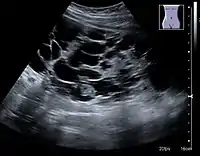

The hydronephrosis is typically graded visually and can be divided into five categories going from a slight expansion of the renal pelvis to end-stage hydronephrosis with cortical thinning (Figure 15). The evaluation of hydronephrosis can also include measures of calyces at the level of the neck in the longitudinal scan plane, of the dilated renal pelvis in the transverse scan plane and the cortical thickness, as explained previously (Figure 16 and Figure 17).[1]

Figure 17. Same patient as in Figure 16 with measurement of the pelvis dilation in the transverse scan plane illustrated on the US image with ‘+’ and a dashed line.[1]